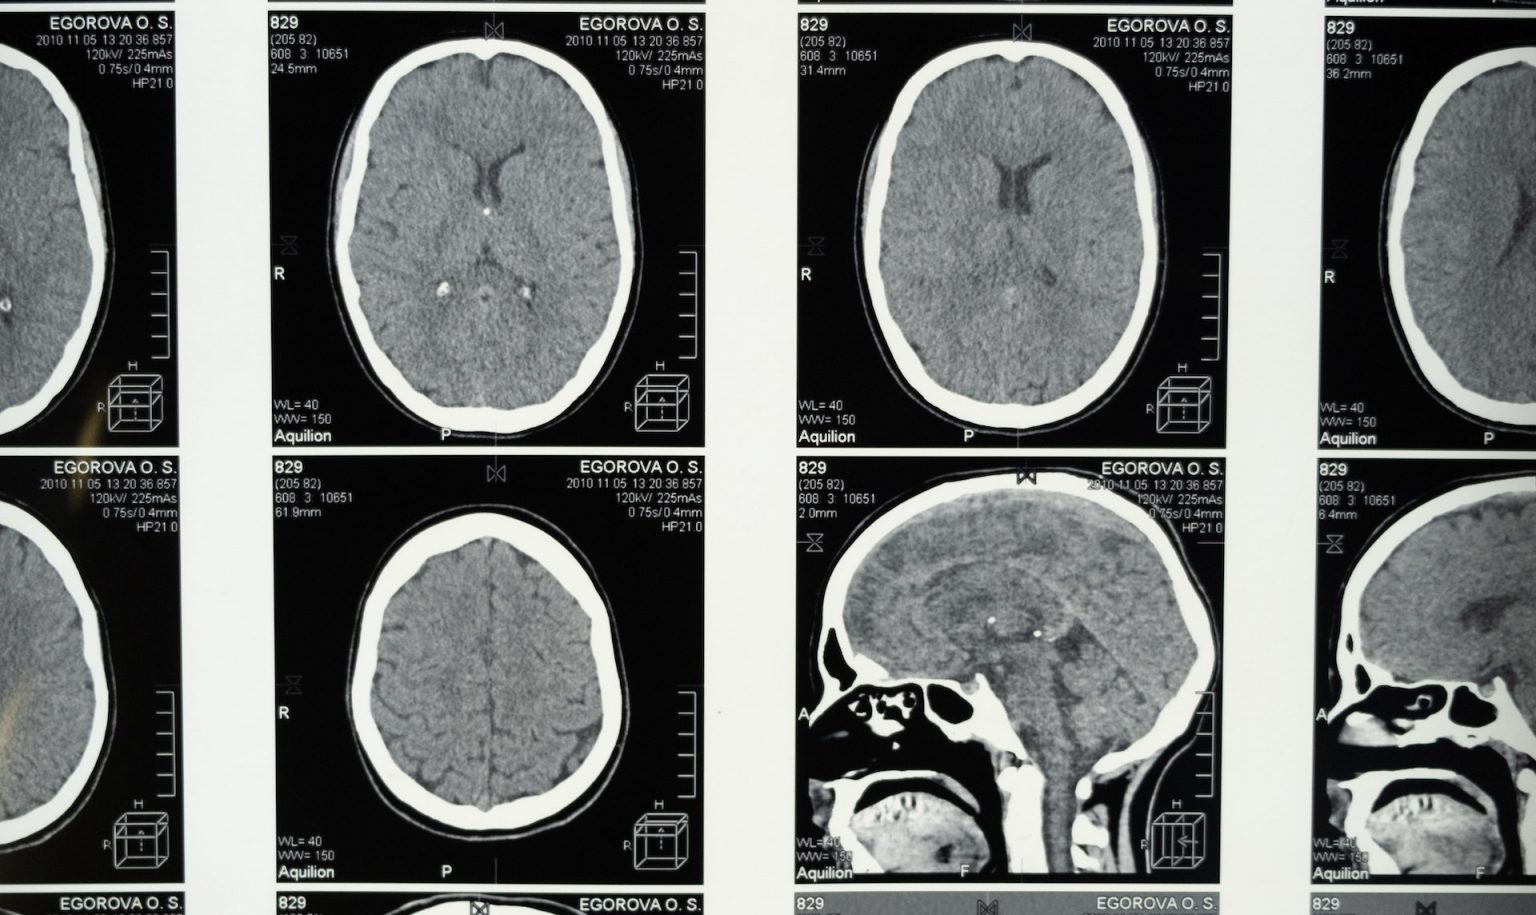

The study used detailed MRI analysis to identify the primary area of lesion overlap, precisely localizing the left medial middle frontal region as the critical filter area.

- Precise anatomical localization using MRI

Lesion overlap analysis identified Brodmann areas 9, 10, and 32 as the critical filter regions within the left medial middle frontal area.